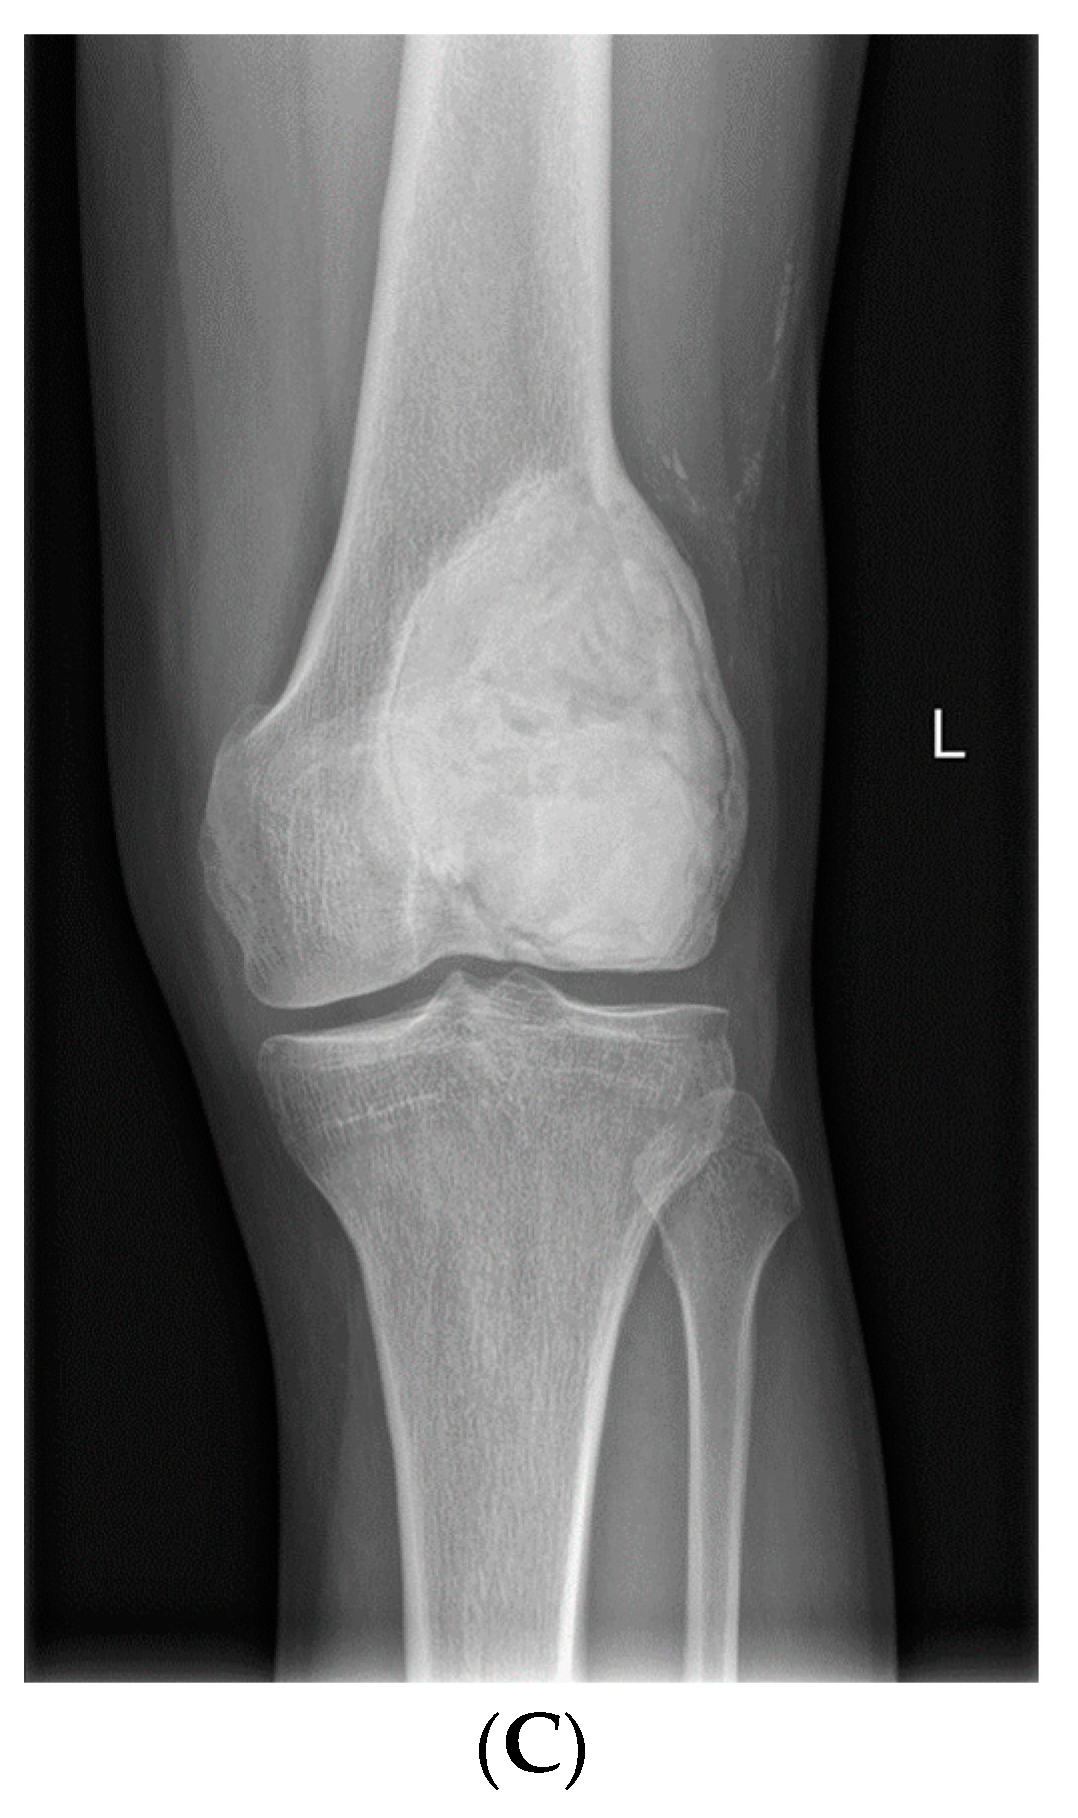

- Van Langevelde, K.; McCarthy, C.L. Radiological findings of denosumab treatment for giant cell tumours of bone. Skelet. Radiol. 2020, 49, 1345–1358. [Google Scholar] [CrossRef] [PubMed]

- Oguro, S.; Okuda, S.; Sugiura, H.; Matsumoto, S.; Sasaki, A.; Susa, M.; Morioka, H.; Jinzaki, M. Giant Cell Tumors of the Bone: Changes in Image Features after Denosumab Administration. Magn. Reson. Med. Sci. 2018, 17, 325–330. [Google Scholar] [CrossRef]

- Hakozaki, M.; Tajino, T.; Yamada, H.; Hasegawa, O.; Tasaki, K.; Watanabe, K.; Konno, S. Radiological and pathological characteristics of giant cell tumor of bone treated with denosumab. Diagn. Pathol. 2014, 9, 111. [Google Scholar] [CrossRef]